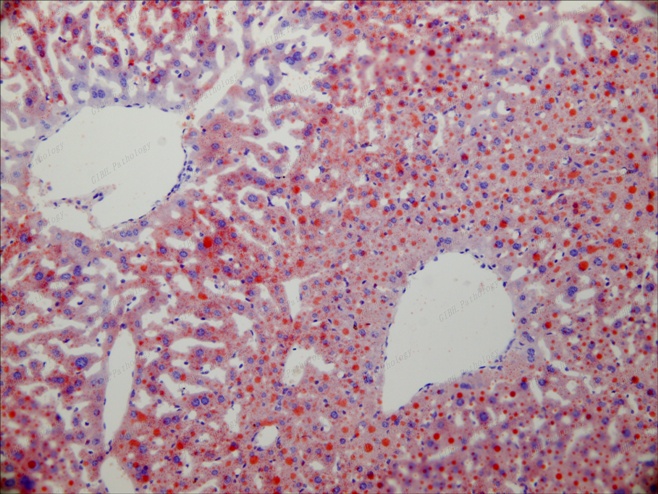

肝髒油紅O染色